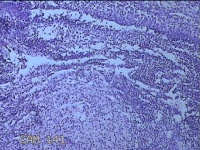

左卵巢囊肿

性别

女

年龄

32岁

临床诊断

左卵巢巧克力囊肿破裂

一般病史

下腹疼痛2天,加重10小时。

标本名称

大体所见

灰白暗红色囊壁样组织5.3x2x1.3cm一堆,表面糜烂,因已切开,囊内容物已流失,囊壁厚0.1cm。

图1